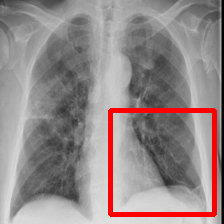

The two infected regions are symmetric.

Fig. 7: Medical image segmentation from QaTa-COV19 dataset. The text annotations are created by hand-craft.

QaTa-COV19: This dataset from Tampere University and Qatar University contains 121,378121378121,378 chest X-ray images (CXRs), including 9258 coronavirus disease 2019 (COVID-19) samples. Each image has a corresponding ground-truth mask for COVID-19 pneumonia segmentation. We choose 50 images as our training set and 10 images as our testing set. In addition, we create the text annotations for this datasets.

Fig. 7 shows the results obtained from experiments on the QaTa-COV19 datasets. Closer inspection of the figure shows that MedT has superiority in depicting long-range information. This benefits from the gated parameters. They can control the amount of information that the positional embedding supplies to key, query and value. It is noteworthy that its ability to learn the local features can still be enhanced.

GTUNet still has trouble capturing local features and depicting the exact edge shape. Inferior to GTUNet, SwinUNet can only produce rough infected regions. However, as shown in Fig. 7, it struggles to catch local details, so some incorrect areas are delineated, and the edge depiction is coarse.

UCTransNet and LViT increase their segmented accuracy. We can observe that they depict the correct infected regions of the first and second IMGs in Fig. 7. What stands out in their result pictures is that they cannot give precise edge information.

Compared with other networks, our model integrates Transformer and CNN into PPE, which ensures that it can obtain meaningful representations. After it has these powerful abilities, we combine PPE and the downstream segmentation tasks. Owing to the pretrained phase and the well-designed decoder, our model presents the most exact segmented results.